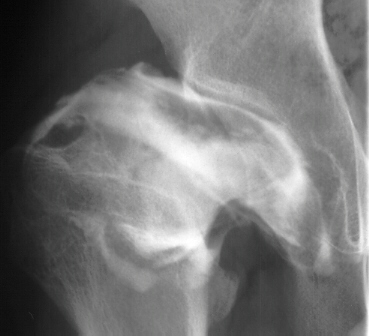

- 2 month Office Follow Up: Rt hip Xray: progressive destruction of capital

femoral epiphysis, cystic changes in metaphysis consistent with AVN.

This case is an example of untreated septic arthritis which caused avascular

necrosis of the proximal femur. The primary cause of this is undrained

septic hip. Repeated aspiration is not adequect treatment of a septic hip.